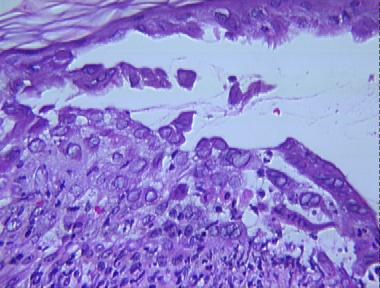

eczema herpeticum

Histologic Features